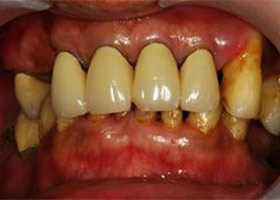

治療前,口內照片。